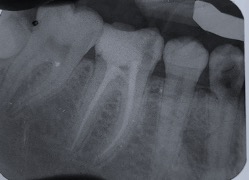

Una corretta terapia canalare con un perfetto sigillo a livello degli apici delle radici è fondamentale. I denti devitalizzati impropriamente possono creare ulteriori problemi che poi andranno a ripercuotersi sulle cure effettuate successivamente come le ricostruzioni e le corone protesiche con conseguente fallimento del piano terapeutico.

Capita spesso di incontrare denti già devitalizzati in maniera impropria che necessitano, seppur asintomatici, di essere ritrattati per evitare che i granulomi infetti visibili radiograficamente si evolvano riassorbendo tutto l’osso sottostante.